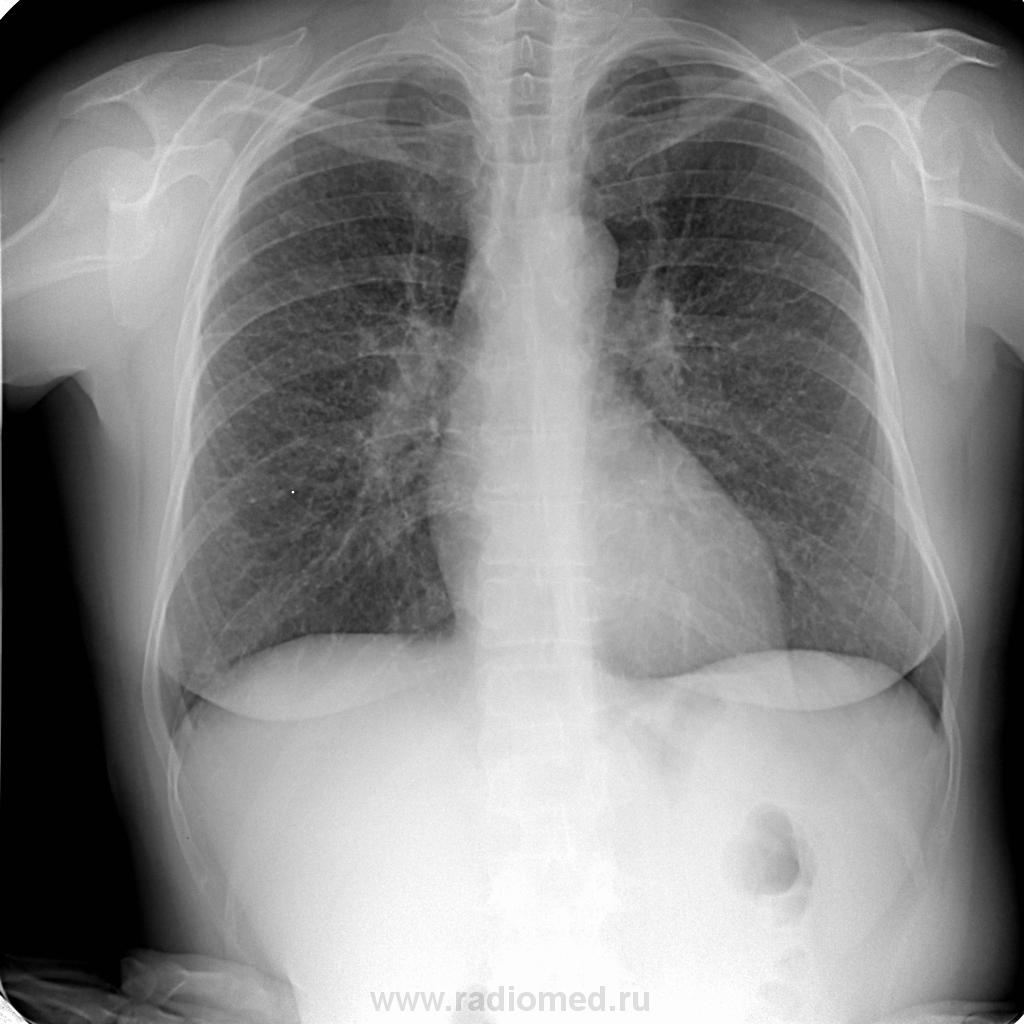

Пациентка 48 лет.Проходила проверочное исследование лёгких. Как интерпритировать данную картину?

Синдром патологии лёгочного рисунка – тёмный глубокий омут.

Мелкоочаговая диссеминация на этом фоне тоже может быть.

Диффузные интерстициальные изменения легких. Не исключается и наличие очаговой диссеминации. Только выполнение СКТ (спиральной компьютерной томографии) может ответить на все Ваши вопросы.

Синдром патологии легочного рисунка (усиление), дифряд: легочная гипертензия, васкулит, клапанный порок сердца. Наличие диссиминации под вопросом, дальнейшая тактика: МСКТ и пусть клиницисты ищут. Мы свое сделали, пациен точно не относится к разряду "почти здоров"! Валентина Львовича выслушать бы и Андрея Юрьевича.

Кроме изменения л/рисунка с признаками диссеминации настораживает снижение прозрачности верхушки правого легкого и неясная тень за 1 ребром над левой ключицей. Выполнила бы задненаклонный снимок верхушек для начала (до СКТ) и хорошенько расспросила бы пациентку. Одолевают смутные сомнения по поводу ее самочувствия.

Такая штука может оказаться саркоидозом, или каким-нибудь пневмокониозом. Без КТ точно не обойтись.

Я по ФЛО предположил пневмокониоз ( можно думать, что и лимфоузлы корней несколько увеличены). Фтизиатры сняли свой DS и поставили в дифряд саркидоз и ещё какое-то системное заболевание ( протокол не видел, только со слов коллеги).

Конечно, во времена СССР, с учетом профанамнеза, на первое место был бы выставлен "пневмокониоз", и не "предстадия", а с учетом милиарной диссеминации, преимущественно в средних и нижних отделах - 1 ст. Конечно сразу бы пациентом прежде всего занялись не фтизиатры, а профпатологи, и не абы как, а регионарное отделение (или институт) профпатологии. Томограммы в таких случаях, при выявлении такой картинки "по флюшке" были бы произведены сразу после рентгенограммы, "на месте". По крайней мере такая тактика имела место быть на "литейных предприятиях". В ряде медсанчастей "литейных предприятий" (МСЧ КЛЗ), в те далёкие времена (был и соответствующий регламент), от проффлюшки отказались и профилактической была обычная стандартная рентгенография в прямой проекции.

Согласна с мнением Андрея Юрьевича по поводу возможного саркоидоза. Против пневмокониозов, любых. ДИЗЛ бывают бессимптомными. На КТ мадам, непременно.

Корни + интерстициально усиленный рисунок минус проф.вредность = ДИЗЛ. Какое - КТ в помощь, да при необходимости биопсия.

Cпасибо, ваша позиция понятна. Строго говоря, имеет  место синдром патологии лёгочного рисунка с интерстициальным компонентом (паттерном в англоязычной терминологии). Требуется дифференциальная диагностика. Показана РКТ лёгких (дальше будет видно, скорее всего, без биопсии лёгкого вряд ли обойдётся).

+1. Диффузный интерстициально-диссеминированный процесс легких. Среди них наибольшую группу составляют больные саркоидозом (63,5%). КТ, по сравнению со стандарт. Ro, может помочь    в дифференциальной диагностике. Однако, несмотря на использование самых современных средств визуализации, включая и КТ (СКТ), точный нозологический диагноз во многих случаях возможен только при морфологическом исследовании (биопсии).

Уверена, что КТ подтвердит саркоидоз ВГЛУ и лёгких (2стадии).

Сегодня пациентке сделана КТ лёгких. Заключение: саркоидоз.Со слов врача, отделения проводившего исследование, имела место лимфоаденопатия внутригрудных лимфатических узлов. Кстати, при анализе топограммы   отмечается некоторая положиельная динамика в сравнении с данными от ноября 2012 г.(лечение не проводили).